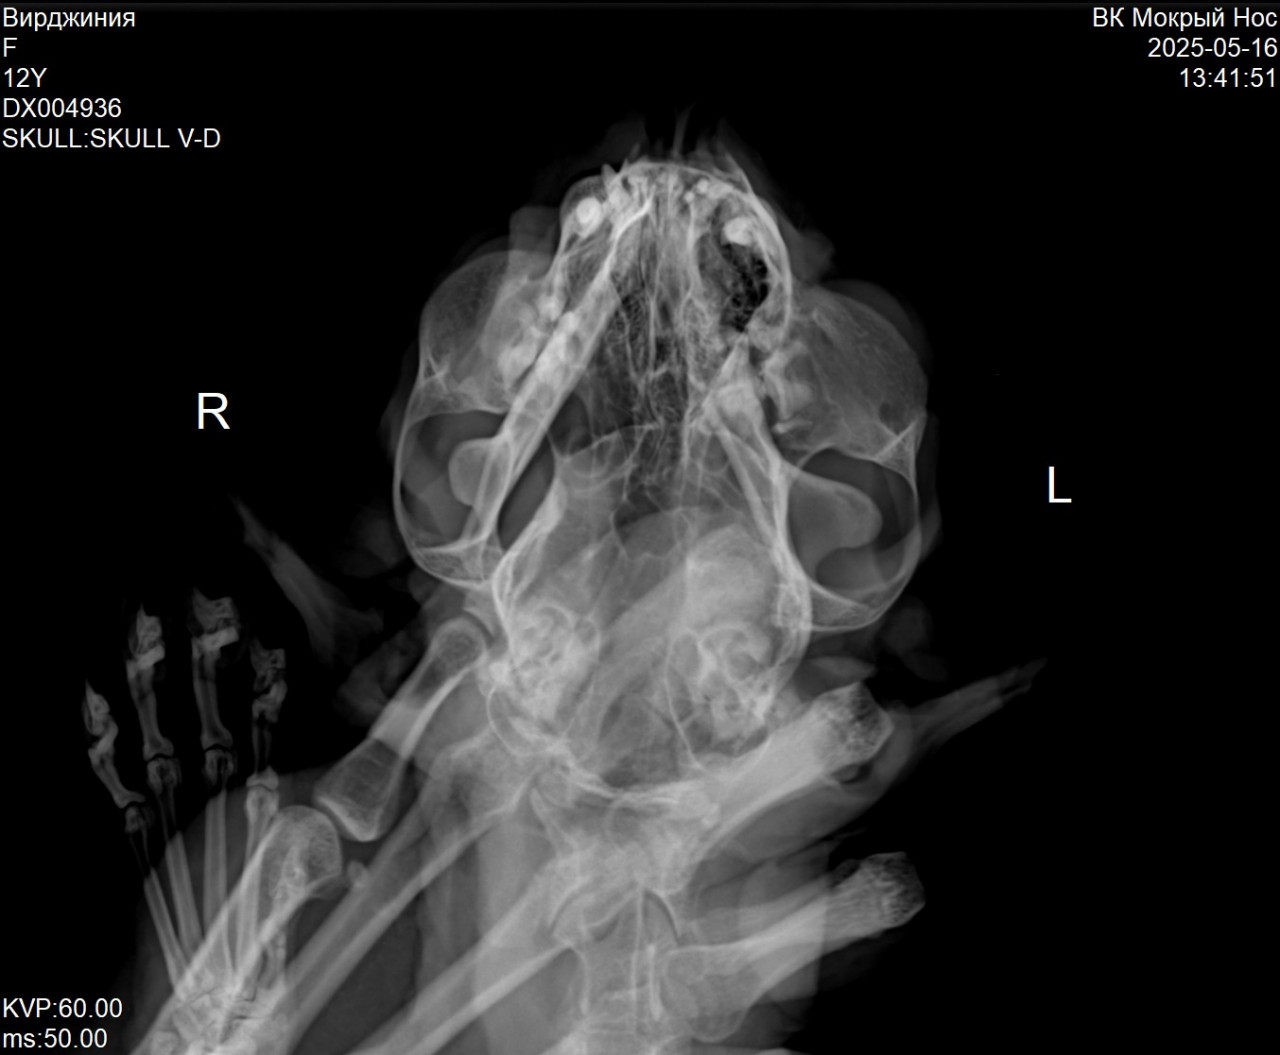

сопли , хрипы носом , все присутствует.  врач сказала онкология судя по снимку (прилагаю)

• Хронические заболевания: онкология аденокарценома молочки и с возможным метостазированием в носоглотку

Здравствуйте. По снимку и всей истории видно, что состояние связано не с ринитом, а,  с опухолевым поражением носоглотки  это подтверждается тяжёлым дыханием, язвой на челюсти, истощением и снимком. АСД-2 теоретически можно использовать, но не в один день с дексаметазоном и флексопрофеном  делайте перерыв 12 часов. Разводится 1 мл на 20-30 мл воды, но применение при онкологии не имеет доказанной эффективности, особенно в такой стадии. На данном этапе основное это паллиативная помощь, обезболивание и поддержка, а не агрессивное лечение. Старайтесь обеспечить кошке комфорт и облегчение.